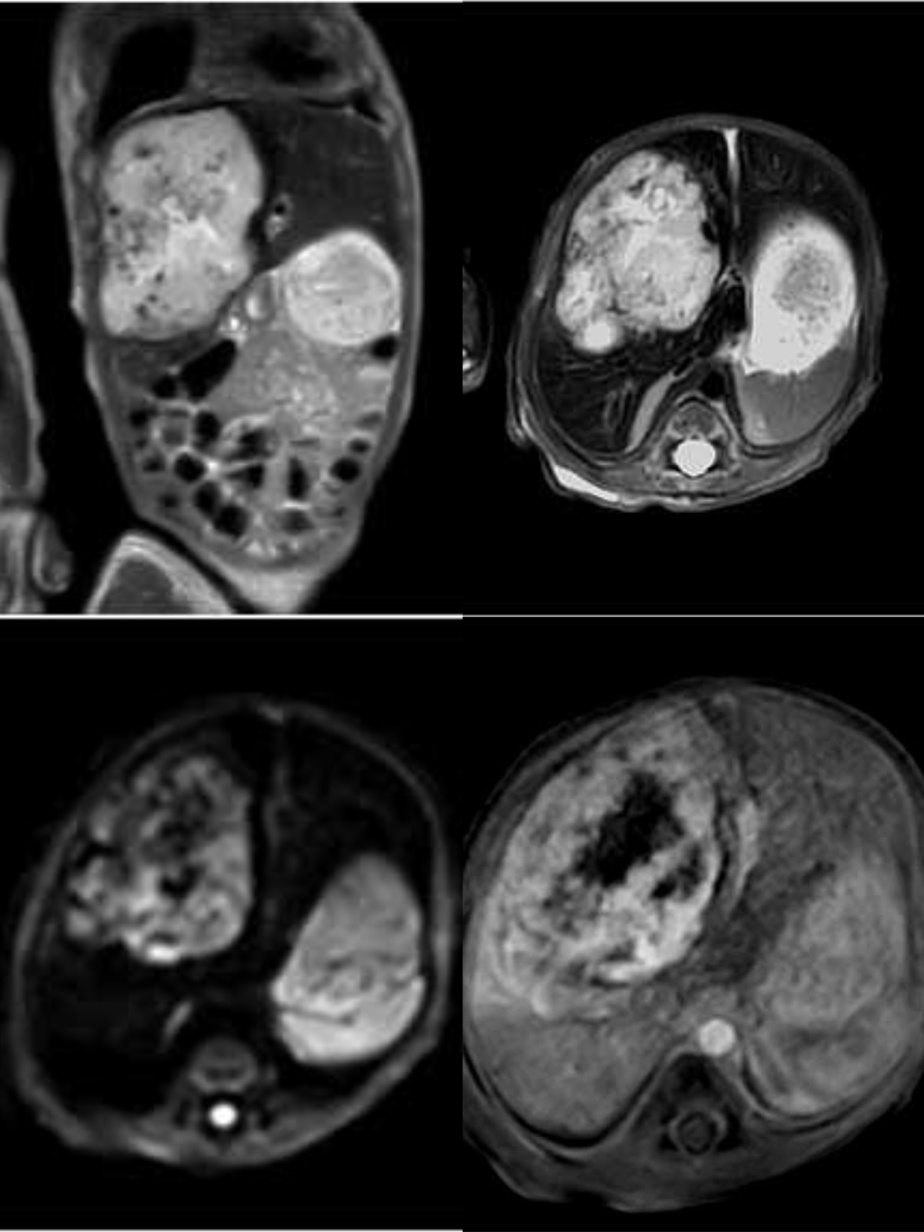

4月29日中午,在新生儿科卢红茹副主任医师和张莉莉主管护师全程保驾护航和雷晓燕主任悉心指导下,张鑫技师长和李娟主管护师、程苗技师在做好前期充分准备工作后,三人默契配合,选择更贴近患儿身体的膝关节线圈,并调整检查序列,克服患儿血管纤细、不时哭闹、无法运用呼吸触发和屏气等重重困难的情况下,仅用时二十分钟,顺利完成了上腹部MRI平扫、动态增强扫描及功能成像(DWI)检查,并获得满意的图像。